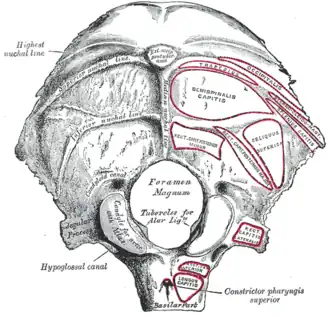

Occipital bone. Outer surface. (Condyloid fossa visible but not labeled.) | |

Human skull seen from below. Position of condyloid fossa shown in red.

Human skull seen from below. Position of condyloid fossa shown in red. -